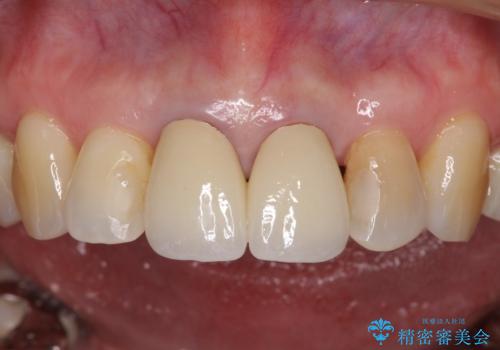

前歯はオールセラミッククラウンに補綴することとしました。

審美面と合わせて清掃性も改善され、患者様には大変満足していただきました。